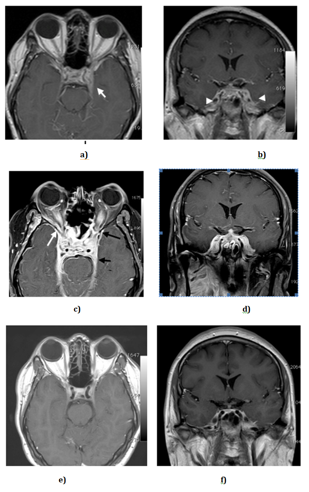

A 33 year old Malay gentleman who presented with left sided headache for 11 days duration. The headache was throbbing and persistent in nature with a Wong and Baker pain score of 9 over 10. It was associated with vomiting of about 5 times a day. A day prior to admission, he experienced blurring of vision. Otherwise, there was no limb weakness or facial asymmetry. Examination revealed isolated left sixth nerve palsy. He was referred to the ophthalmology team and further eye examination revealed no papilledema. He was also referred to the ENT team which revealed normal ENT findings. CT brain plain done showed no abnormality. MRI brain done showed no evidence of tumour or infarct (Figure 1a,1b). Patient had refused lumbar puncture and had taken discharge at own risk to seek alternative medicine. He was readmitted four days later with worsening of double vision. Examination revealed bilateral eye 3rd, 4th. and 6th nerve palsy. Otherwise there was no limb weakness and there was no pulmonary findings. Erythrocyte sedimentation rate was elevated at 100 mm/Hr. Further screening test such as sputum for acid fast bacilli (AFB), Chest X-ray and Mantoux test were negative. Additional tests such as FBC, Renal profile and liver function test was normal. He was tested negative for human immunodeficiency virus (HIV) (Table 2). Repeated MRI brain revealed inflammatory changes involving bilateral cavernous sinus and surrounding regions, which favour central nervous system (CNS) infection or granulomatous disease (Figure 1c-1d).

He had repeated MRI scan 2 months after anti TB treatment which revealed complete resolution of previous inflammatory changes (Figure 1e,1f). Patient was reviewed after 2 months of starting anti TB and currently the isolated sixth nerve palsy has resolved. Also, there was no more headache. He will be reviewed again in sixth month time (eight month of anti TB). He is planned for standard of 12 months anti TB treatment as per TB meningitis protocol.4

Figure 1 Axial and Coronal post-contrast T1-weighted images at initial presentation (a-b), at one week(c-d) and at 2 months (e-f) interval.

First row (a-b): Initial MR Brain images show evidence of inflammatory change largely confined to the cavernous sinus (short white arrowhead); the left cavernous sinus is enlarged (white arrow).

Second row (c-d): The MRI images show increasing inflammatory change with extensive enhancement and enlargement of both cavernous sinus extending to the orbital apex (small black arrow) and temporal regions (white arrow) anteriorly, and Meckel’s cave (black arrowhead) posteriorly.

Third row (e-f): MRI images 2 months later shows significant resolution of the inflammatory change.